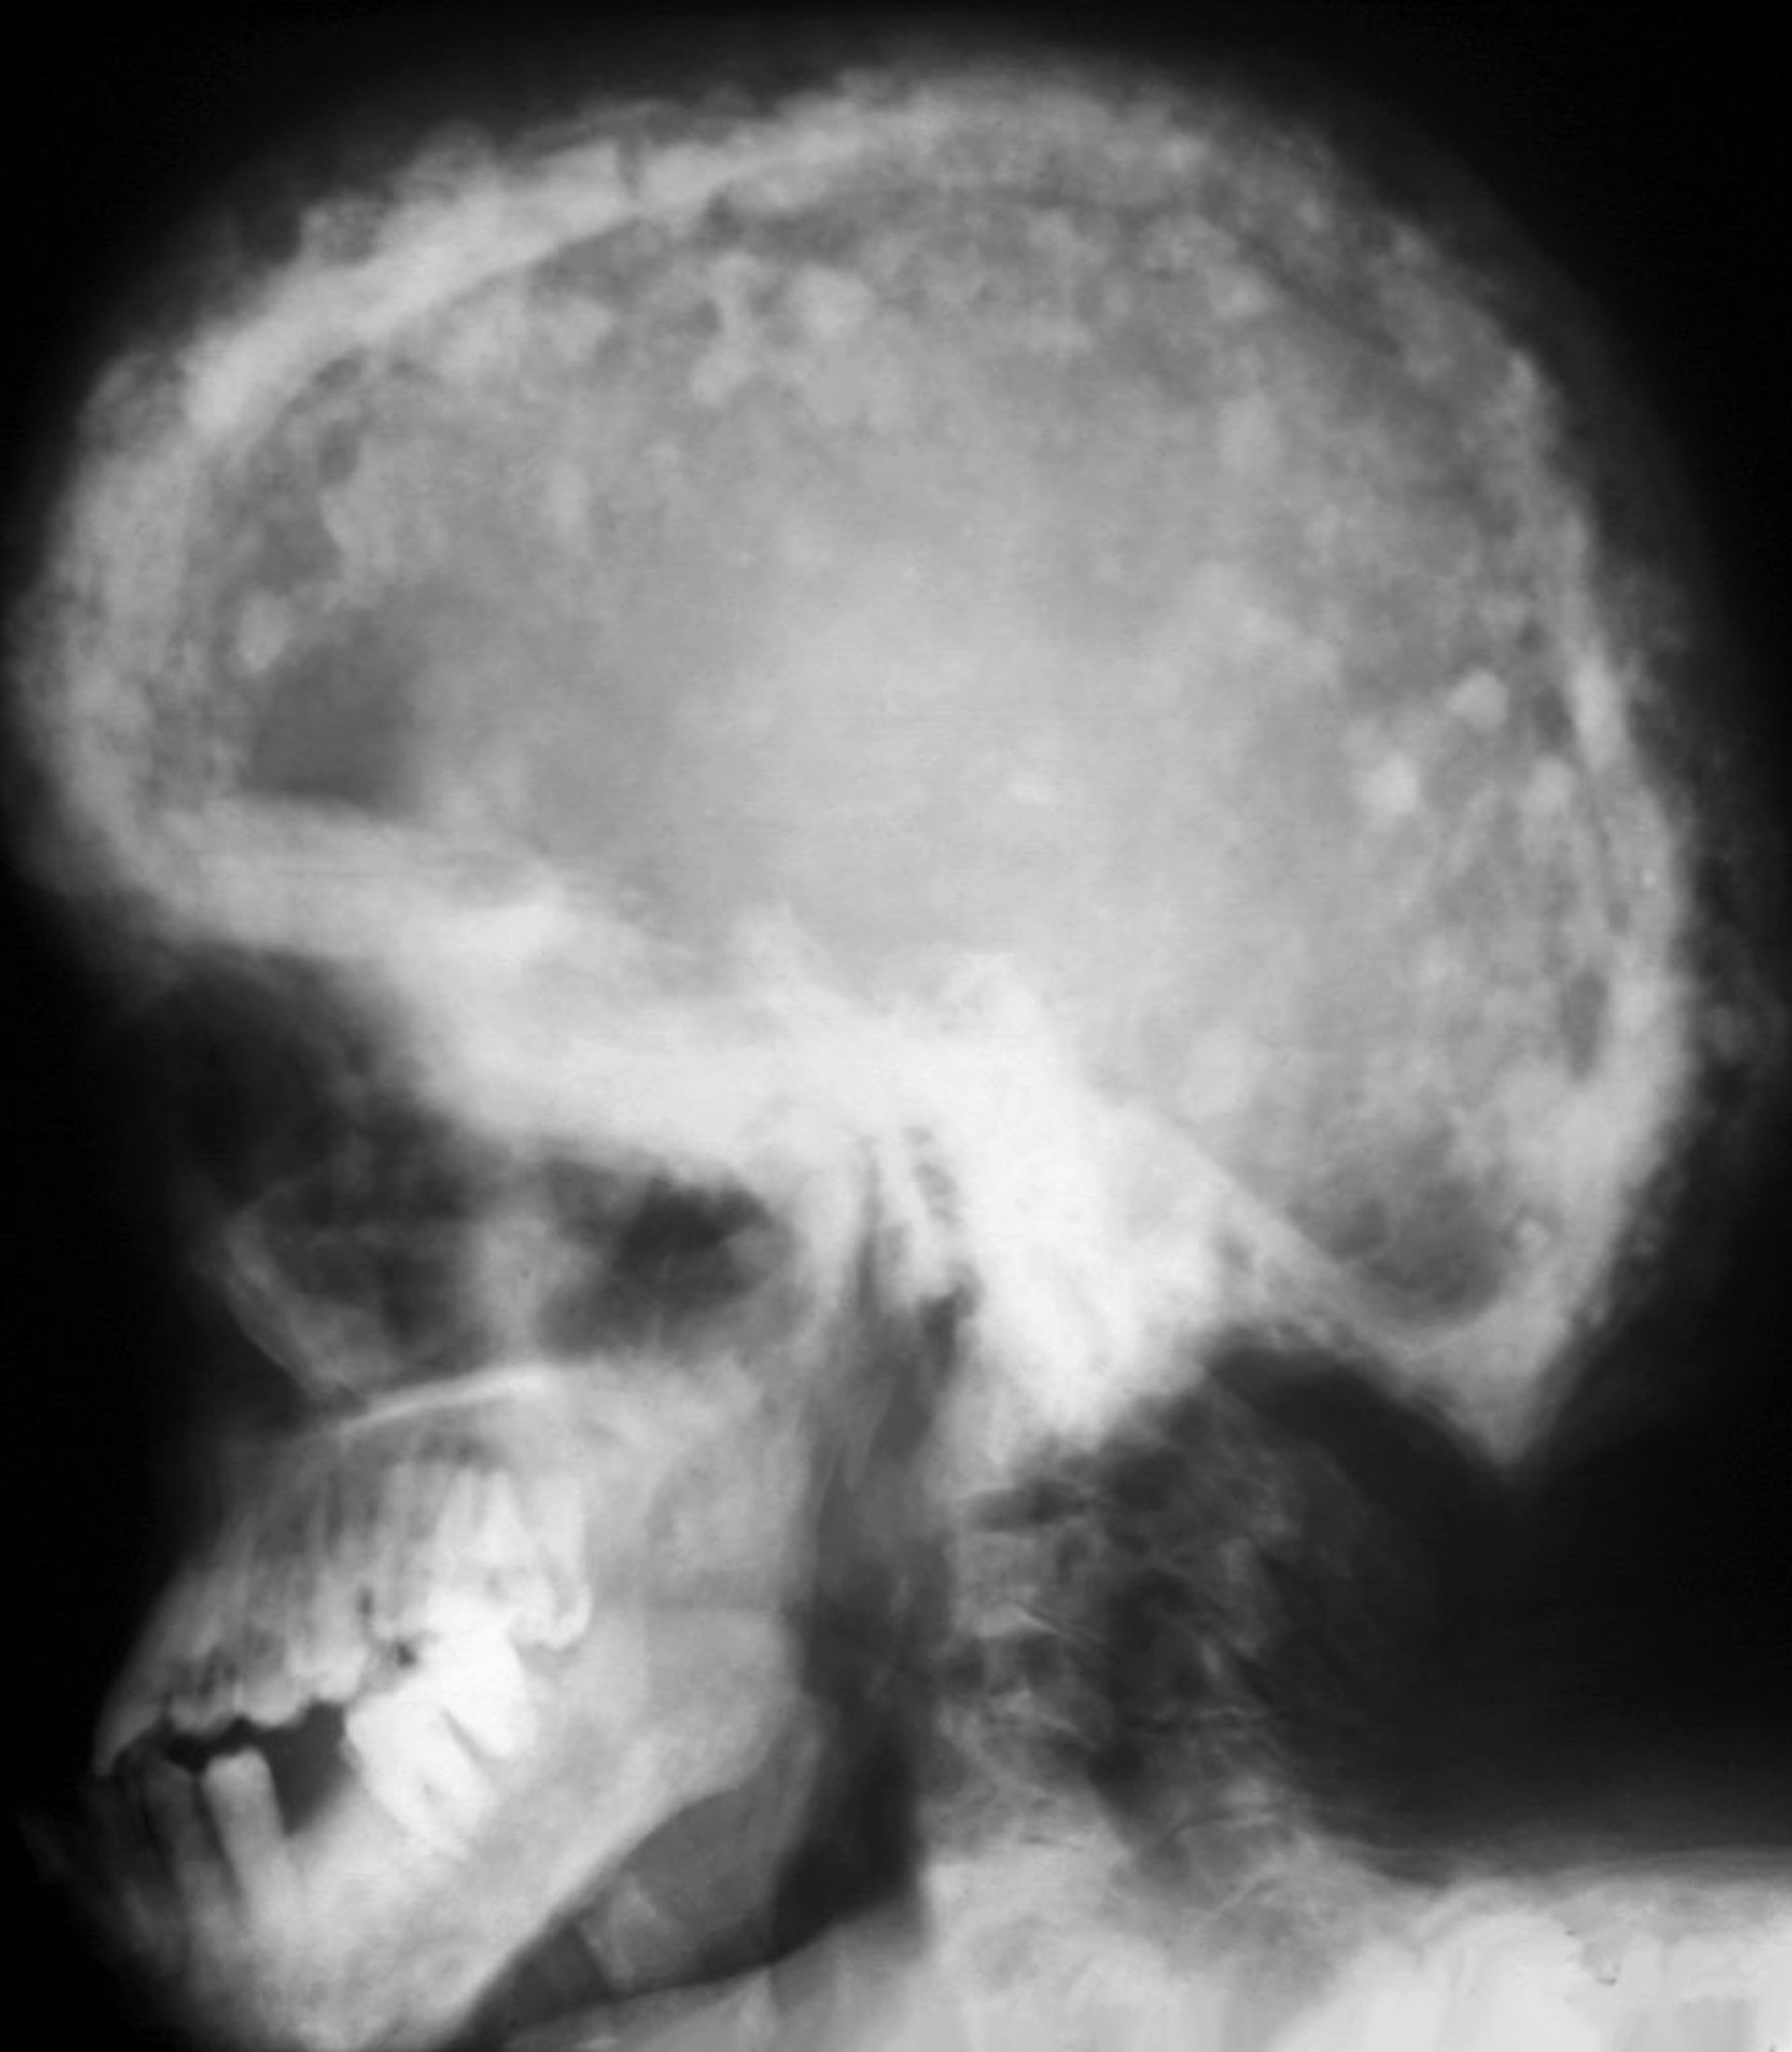

Radiographie du crâne dans la maladie de Paget

Un aspect de mosaïque typique des zones de sclérose et de radiotransparence accrues est visible sur cette radiographie. Ces taches cotonneuses résultent de l'épaississement du calvarium.